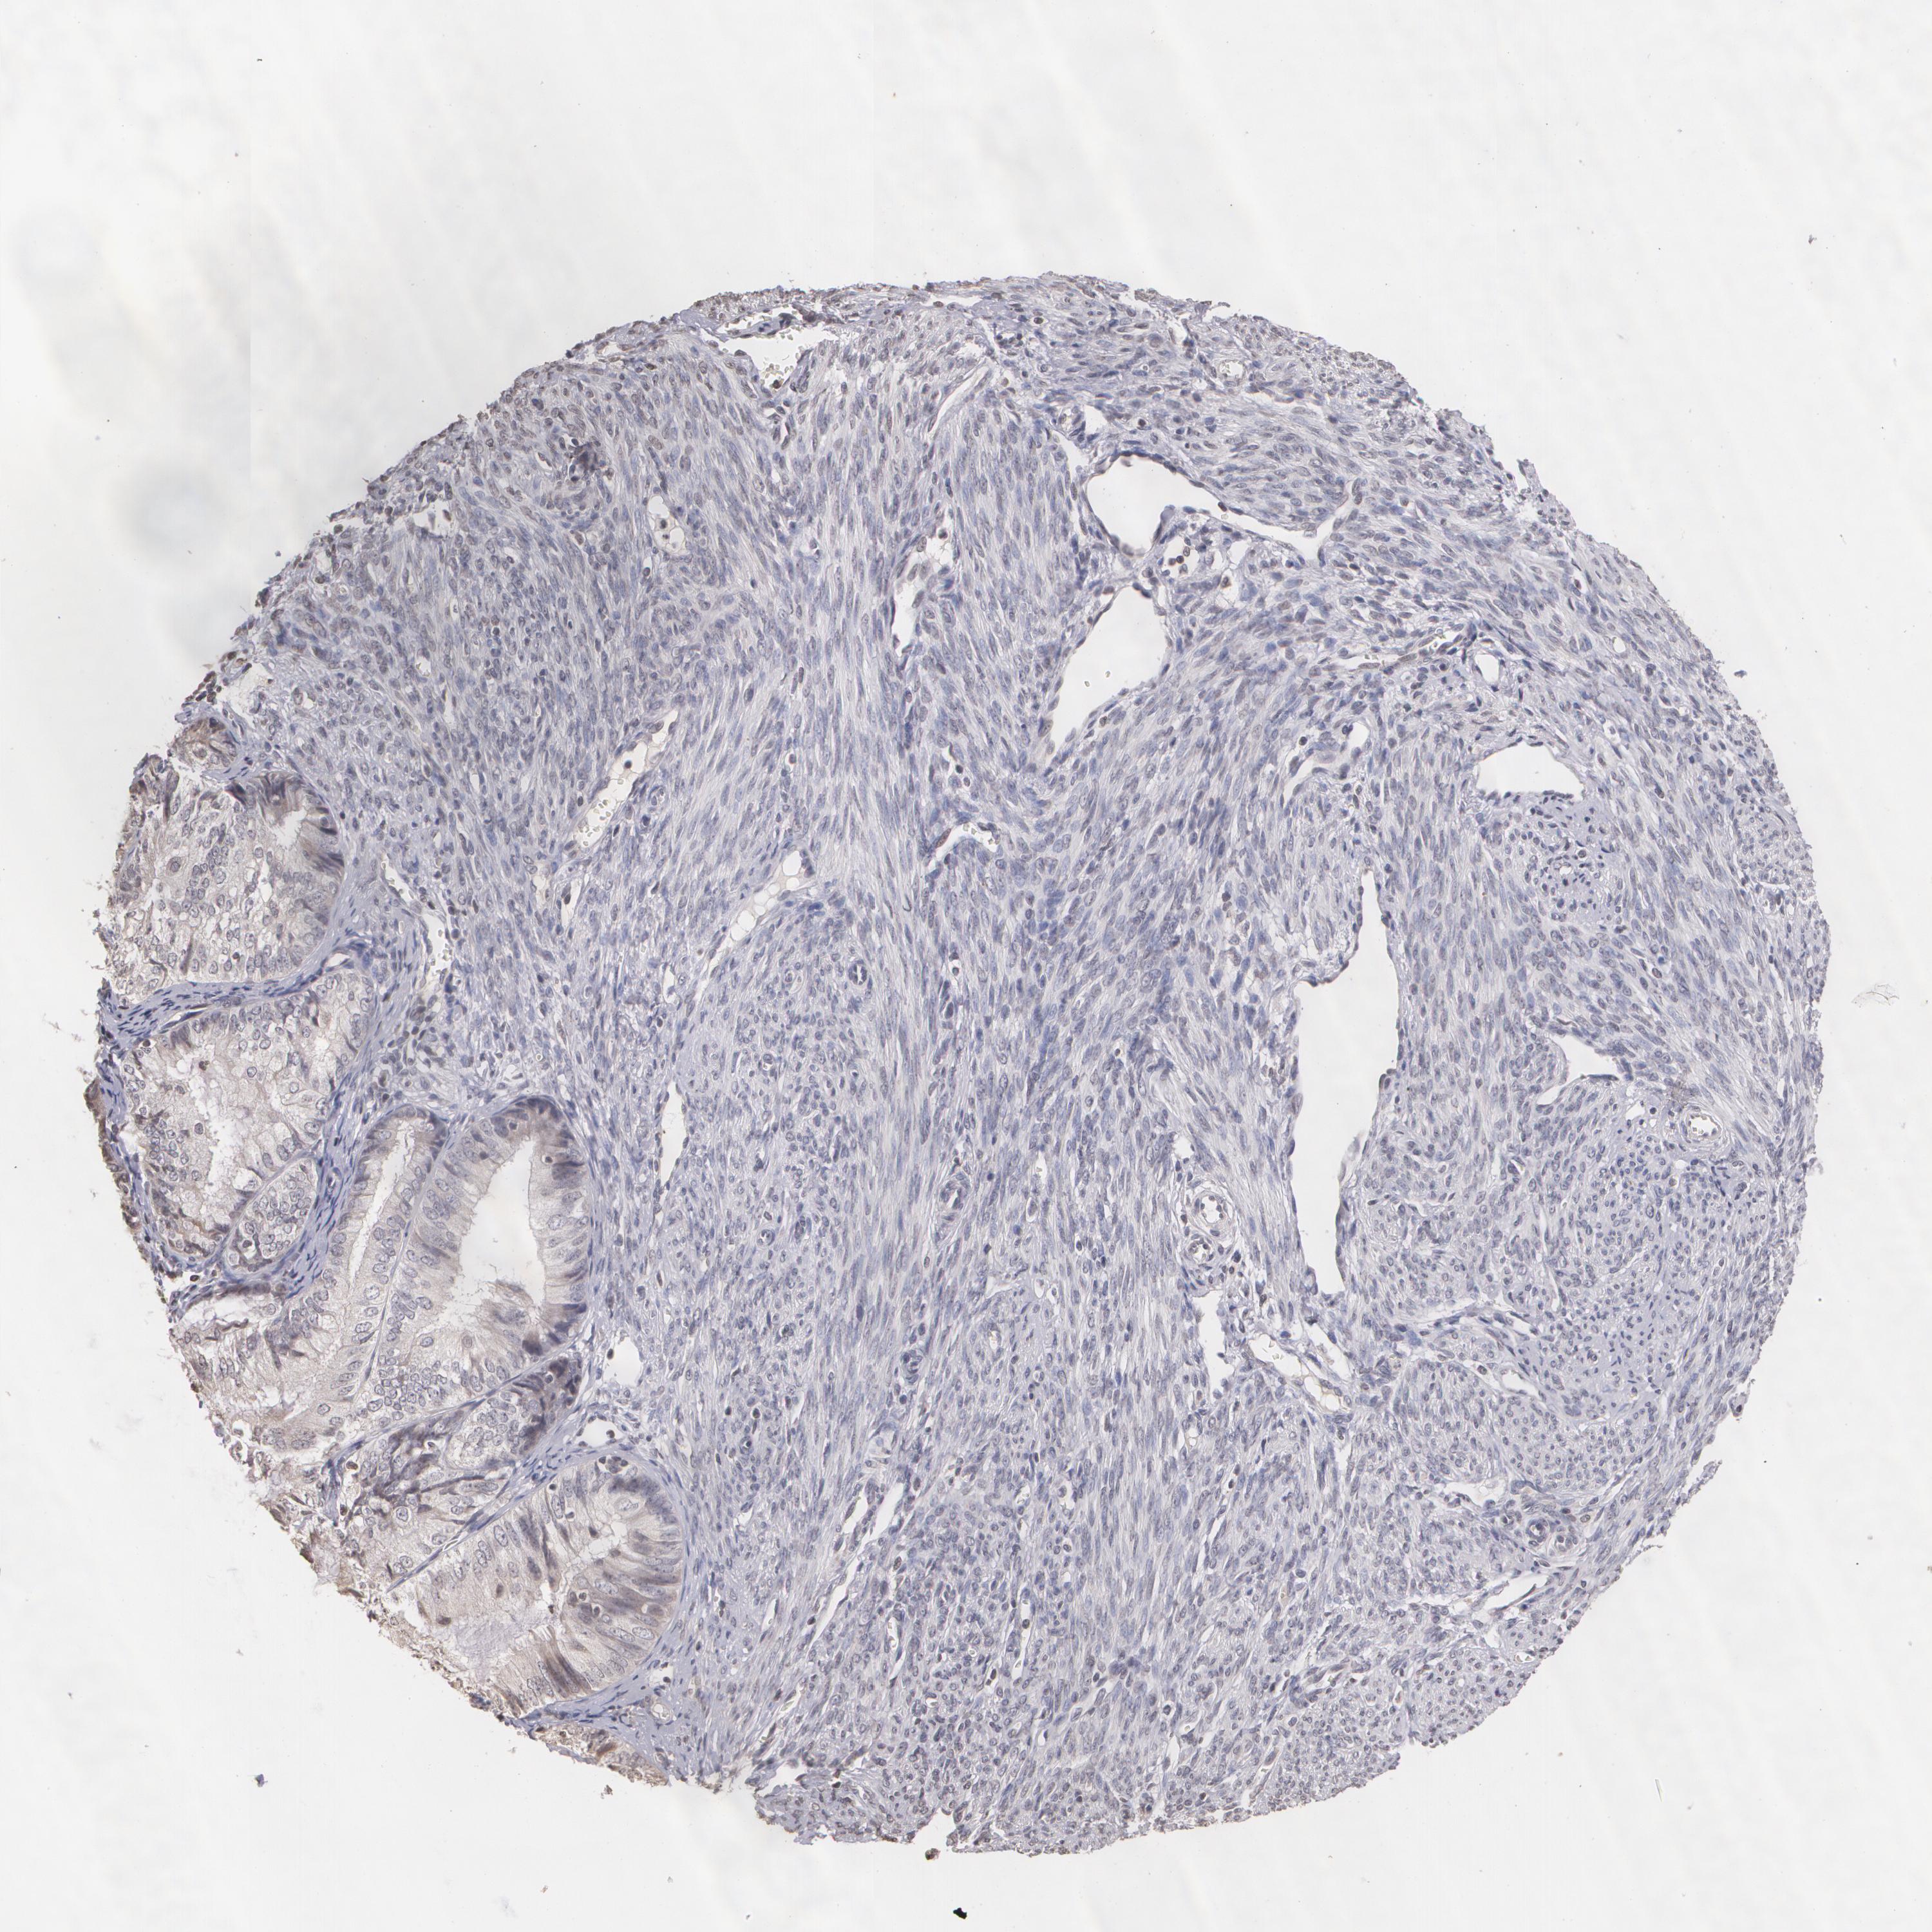

ENDOMETRIAL CANCER - Protein expressioni

A mouse-over function shows sample information and annotation data. Click on an image to view it in a full screen mode. Samples can be filtered based on level of antibody staining by selecting one or several of the following categories: high, medium, low and not detected. The assay and annotation is described here.

Note that samples used for immunohistochemistry by the Human Protein Atlas do not correspond to samples in the TCGA dataset.

Antibody stainingi

Antibody staining in the annotated cell types in the current human tissue is reported as not detected, low, medium, or high, based on conventional immunohistochemistry profiling in selected tissues. This score is based on the combination of the staining intensity and fraction of stained cells.

Each image is clickable and will lead to virtual microscopy that enables deeper exploration of all samples and also displays staining intensity scores, fraction scores and subcellular localization as well as patient and tissue information for each sample.

Antibody CAB002008

Antibody CAB002009

Staining

High

Medium

Low

Not detected

Intensity

Strong

Moderate

Weak

Negative

Quantity

>75%

75%-25%

<25%

None

Location

Nuclear

Cytoplasmic/membranous

Cytoplasmic/membranous,nuclear

Adenocarcinoma, NOS